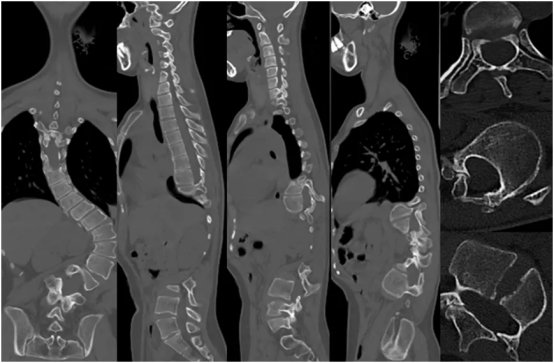

在海南医科大学第一附属医院脊柱外科病房的走廊,24岁的小符(化名)静静伫立,窗外灿烂的阳光倾洒而入,她第一次真切地感受到,未来满是光明与希望。就在短短两周前,严重的脊柱侧弯还让她无法挺直腰杆,连正常呼吸都成了奢望。如今,经过头盆环牵引治疗,她的脊柱侧弯角度从92.3°锐减至56.7°,身体状况显著改善,而这一切的改变,都始于她踏入海南医科大学第一附属医院的那一刻。小符自幼便察觉到自己与其他孩子的不同,她的...